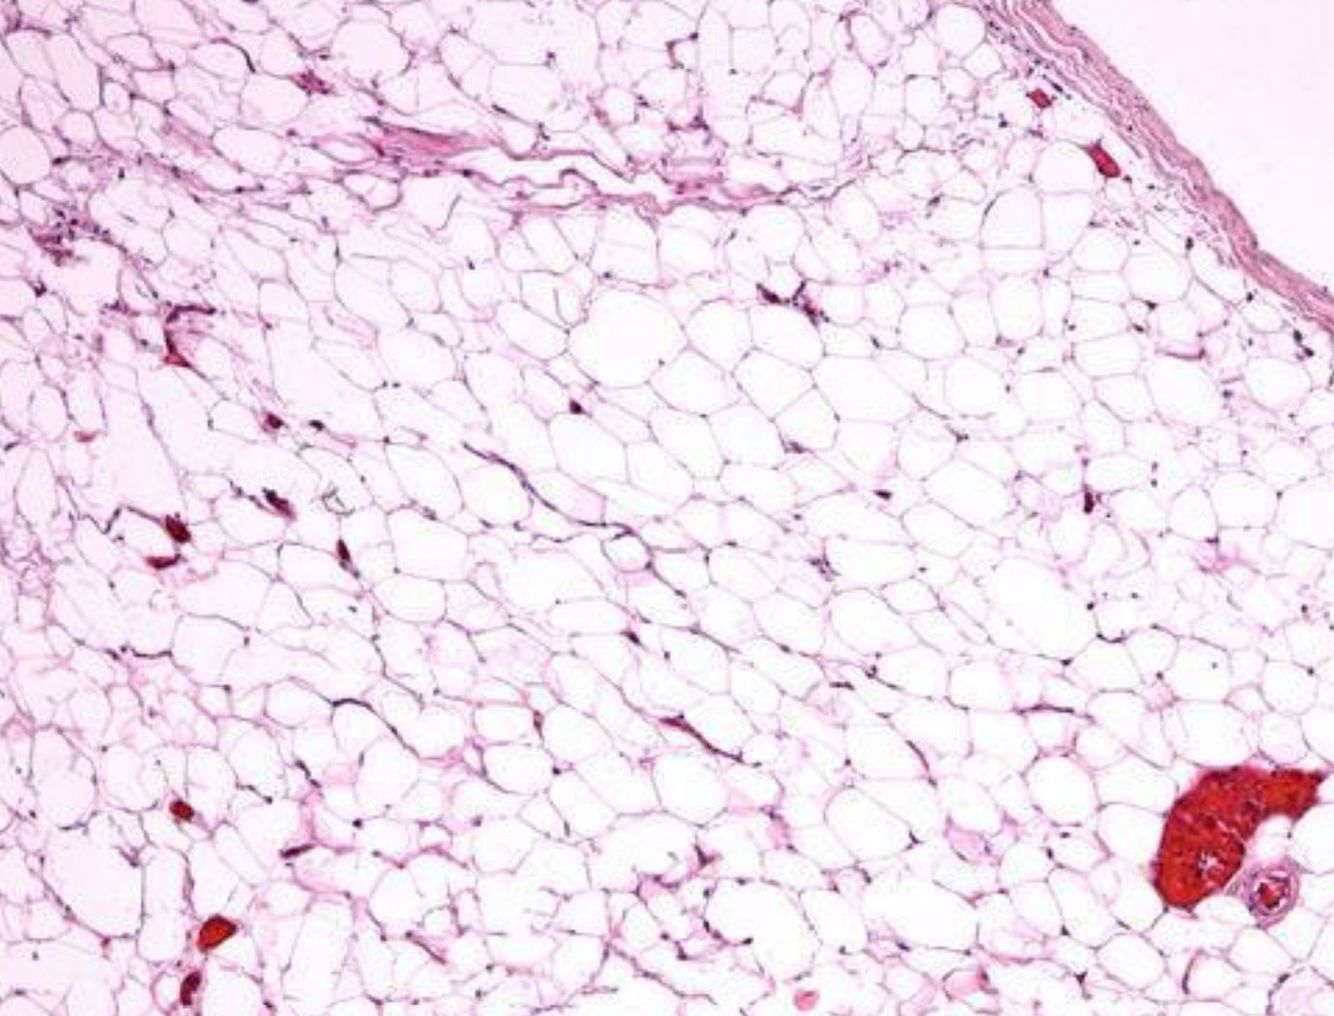

Lipoma

A benign tumor. Upon histological examination, the lipoma looks almost exactly like regular hyperplastic fat. There is little if any ongoing mitosis, no necrosis, and no hemorrhage.